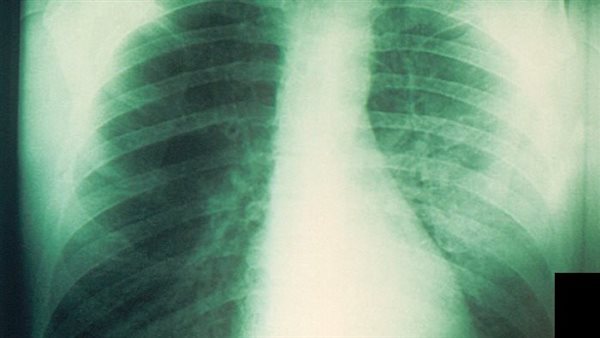

دراسة: تفوق اختصاصيي الأشعة على الذكاء الاصطناعي في تشخيص أمراض الرئة الشائعة باستخدام الأشعة السينية

وجدت دراسة جديدة، أن استخدام الذكاء الاصطناعي، يساعد في تعزيز ثقة أطباء الأشعة في تشخيصاتهم، ولكن لا يمكن الاعتماد عليها لتحديد أمراض الرئة الشائعة من خلال الأشعة السينية للصدر.

ووضع الباحثون 72 متخصصًا في الأشعة في مواجهة أربع أدوات ذكاء اصطناعي متاحة تجاريًا لتحليل أكثر من 2000 صورة أشعة سينية، وذلك وفقًا لدراسة نشرت في مجلة الأشعة.

وفي الدراسة، تم إجراء الأشعة السينية على مدار عامين في أربعة مستشفيات دنماركية، ونحو ثلثهم لديهم تشخيص مستهدف واحد على الأقل.

وكانت لأدوات الذكاء الاصطناعي معدلات حساسية تتراوح بين 72% إلى 91% لأمراض المجال الجوي، ومن 63% إلى 90% للصدر، ومن 62% إلى 95% للانصباب الجنبي.

ووجدت الدراسة أن أخصائي الأشعة تفوقوا على الذكاء الاصطناعي في التحديد الدقيق لأمراض الرئة الثلاثة الشائعة.

وقال المؤلف الرئيسي للدراسة الدكتور لويس بليسنر، إن التصوير الشعاعي للصدر أداة تشخيصية شائعة، ولكن هناك حاجة إلى قدر كبير من التدريب والخبرة لتفسير الاختبارات بشكل صحيح.

وتابع: كان أداء الذكاء الاصطناعي هو الأسوأ في تحديد أمراض الصدر، حيث تراوحت القيم التنبؤية الإيجابية بين 40% و50%، وهدف أخصائيو الأشعة هو تحقيق التوازن بين اكتشاف المرض واستبعاده، وتجنب الأمراض الكبيرة التي يتم التغاضي عنها.